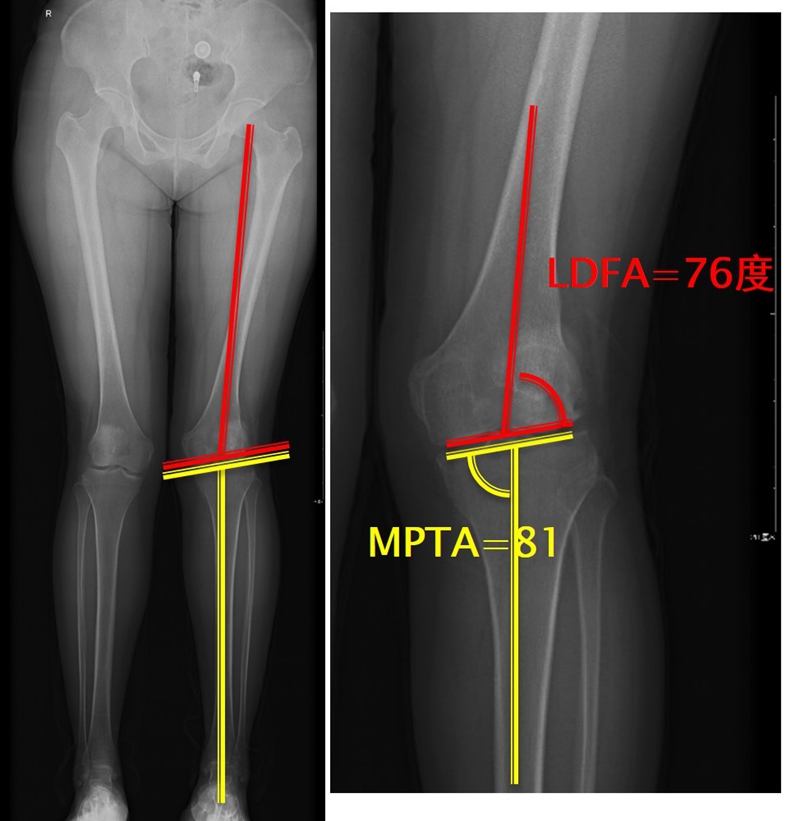

量股骨远端外侧角和胫骨近端内侧角,判断畸形在股骨、胫骨还是关节内。此患者股骨侧有畸形,LDFA=76°,MPTA=81°,无关节内畸形。

此患者计划股骨内侧闭合楔,胫骨内侧开放楔。

以股骨侧合页为旋转中心,以股骨头中心到合页的距离为半径,进行旋转,直到该线段与目标力线相重合,此时重合角度即为股骨需要闭合的角度,同时胫骨侧也能计算出开放的角度。此患者需要股骨闭合14°,胫骨开放8°。